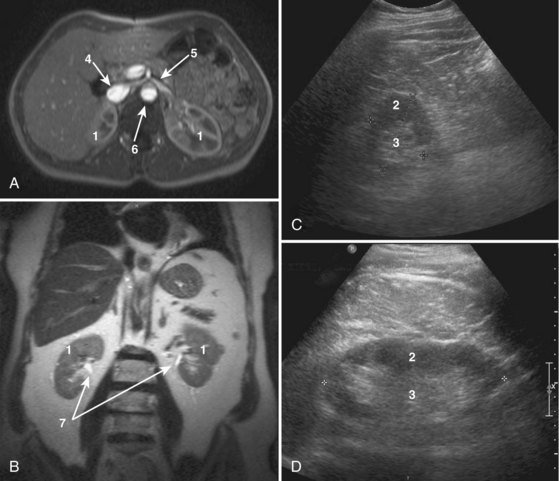

Many of these gross anatomic structures can be seen on modern imaging modalities such as computed tomography (see Fig. 1–11), as well as ultrasound and magnetic resonance imaging (Fig. 1–23).

Figure 1–23 Cross-sectional imaging of the normal kidney. A, T1-weighted gadolinium-enhanced axial magnetic resonance imaging (MRI) of kidneys including the inferior vena cava, aorta, left renal vein, and superior mesenteric artery. B, Coronal T2 MRI of the kidneys. C, Transverse ultrasound imaging of the kidney. D, Sagittal ultrasound imaging of the kidney. 1, Kidney. 2, Renal cortex. 3, Renal medulla. 4, Inferior vena cava. 5, Left renal vein. 6, Aorta. 7, Renal collecting system.